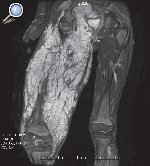

El neurofibroma plexiforme tiene una apariencia patognomónica. Se observa como una nodularidad difusa de todo el recorrido del nervio y sus ramas, con una hiperintensidad similar al agua en las secuencias ponderadas en T2. Los de gran volumen reemplazan el tejido adiposo creando una apariencia en «panal». Clínicamente se manifiestan por elefantiasis neuromatosa37, 38, 39 (Figura 6).

Figura 6. Niño de 14 años, con antecedente de neurofibromatosis tipo I. Secuencia SSFSE ponderada en T2 en el plano coronal del muslo, en la que se observa una formación voluminosa en las partes blandas del muslo, con alta intensidad de señal, polilobulada, con múltiples septos. La biopsia demostró un neurofibroma plexiforme del nervio ciático.